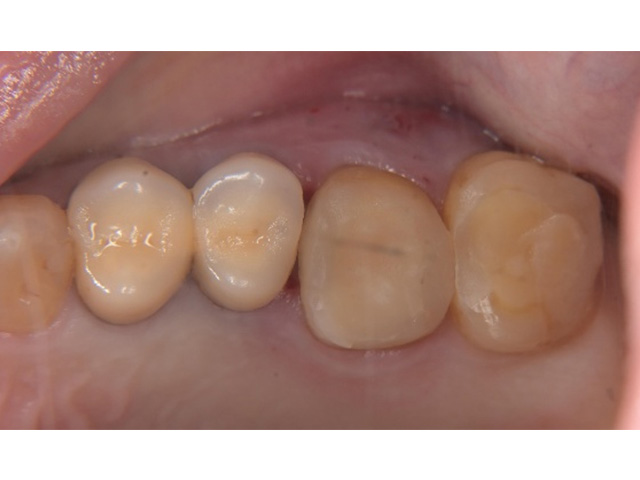

Before

親知らず移植後当日

After(移植後2か月)

After(移植後2か月)2

| 主訴 | 左下の奥歯がズキズキ痛む |

|---|---|

| 治療内容 | 左下第一大臼歯抜歯し左下智歯(親知らず)移植後の根管治療 |

| 治療回数・期間 | 7回(3か月)※根管治療は2回 |

| 費用 | 保険適応 |

| リスク・副作用 | 根管治療は術前の精密な診査診断および無菌環境下での治療によって成功率は高まってきましたが治療の成否を決める多くの要素があるため、根管治療がなされた後も再治療や外科処置、抜歯となる可能性が少なからずあります。また治療中には器具の破折や穿孔、修復物の損傷、歯の破折、術中・術後の痛みや腫れが生じることが稀にあります。根尖病変(再感染)を防ぐには適合の良好な補綴物を作製することや定期的なかみ合わせのチェックが必要です。 |